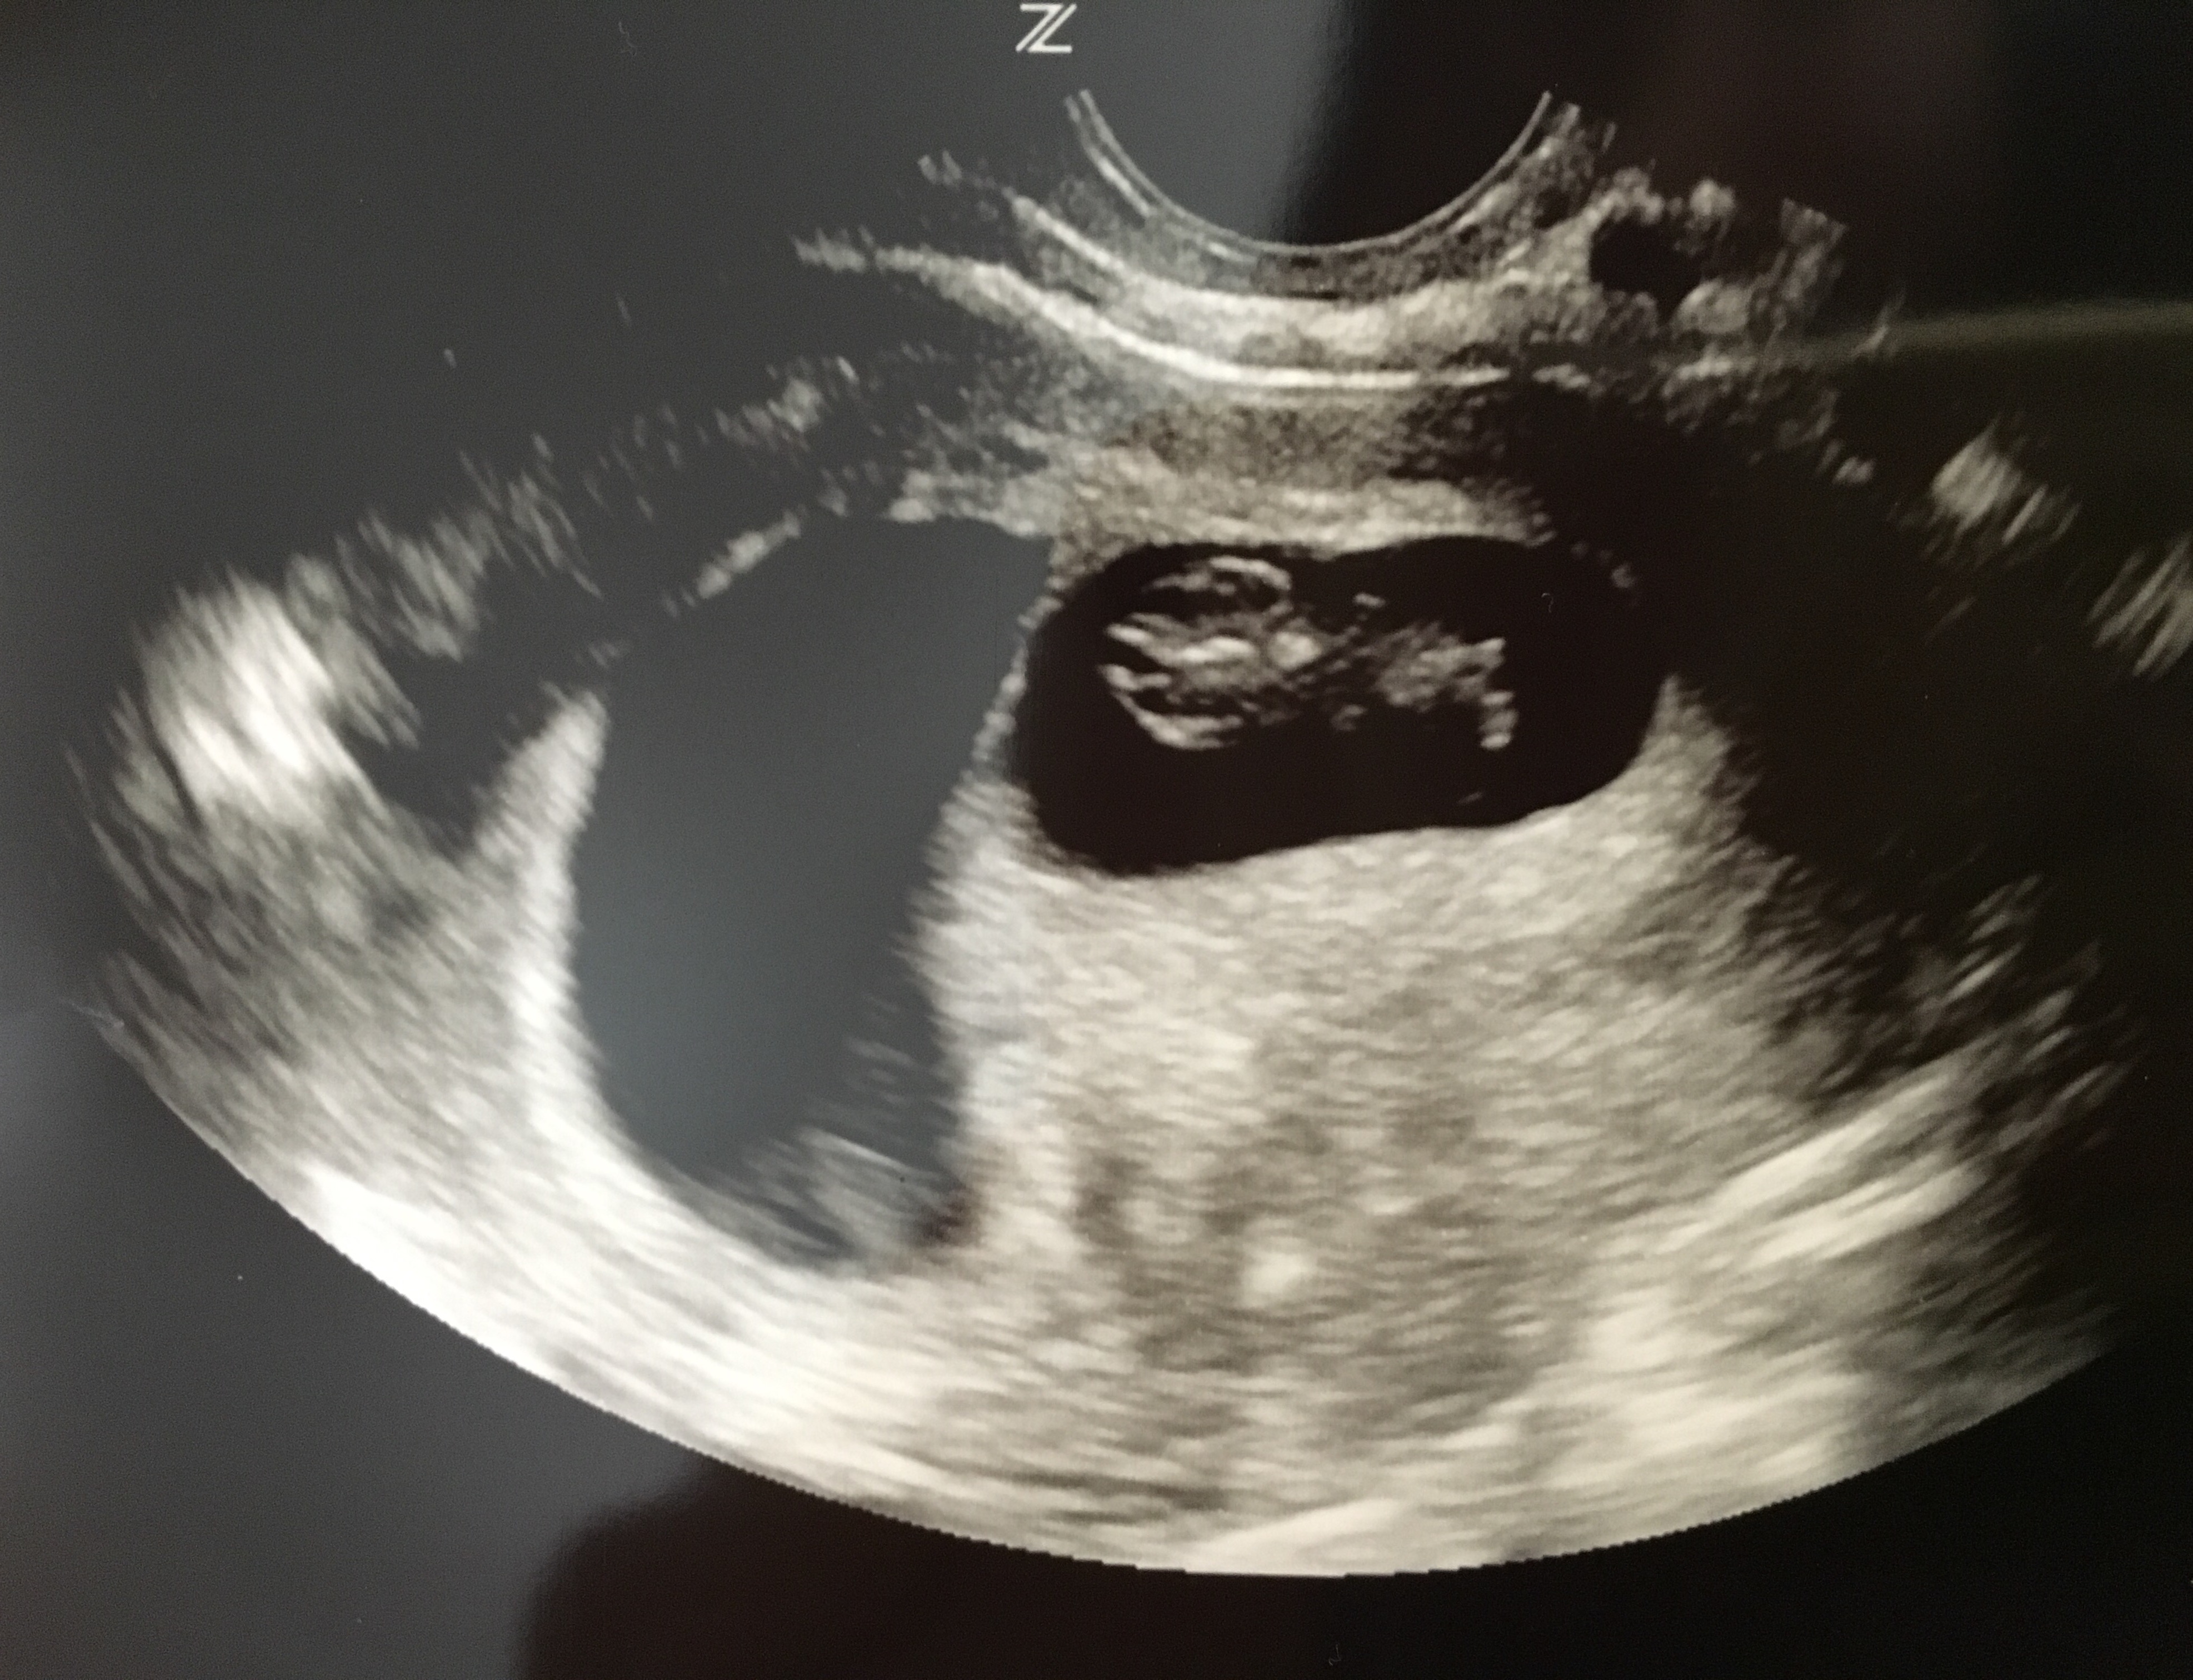

I had my second u/s on Tuesday at 8 weeks and 6 days. The baby is still measuring three days behind but they have not changed my edd. It was great to see how big the baby has gotten and to see its heart still beating. I go back on the 23 for some genetic testing and I get an u/s at that appointment, which was a great surprise to hear that. The equipment at the new place I have to go to is so much better than what my doctor has. Im hoping I can actually hear the heart beat at that appointment. I have not been able to hear it or to know how many bpm it is. But here is my little bean!

Btw I have no clue what those white lines are and neither does my doctor.